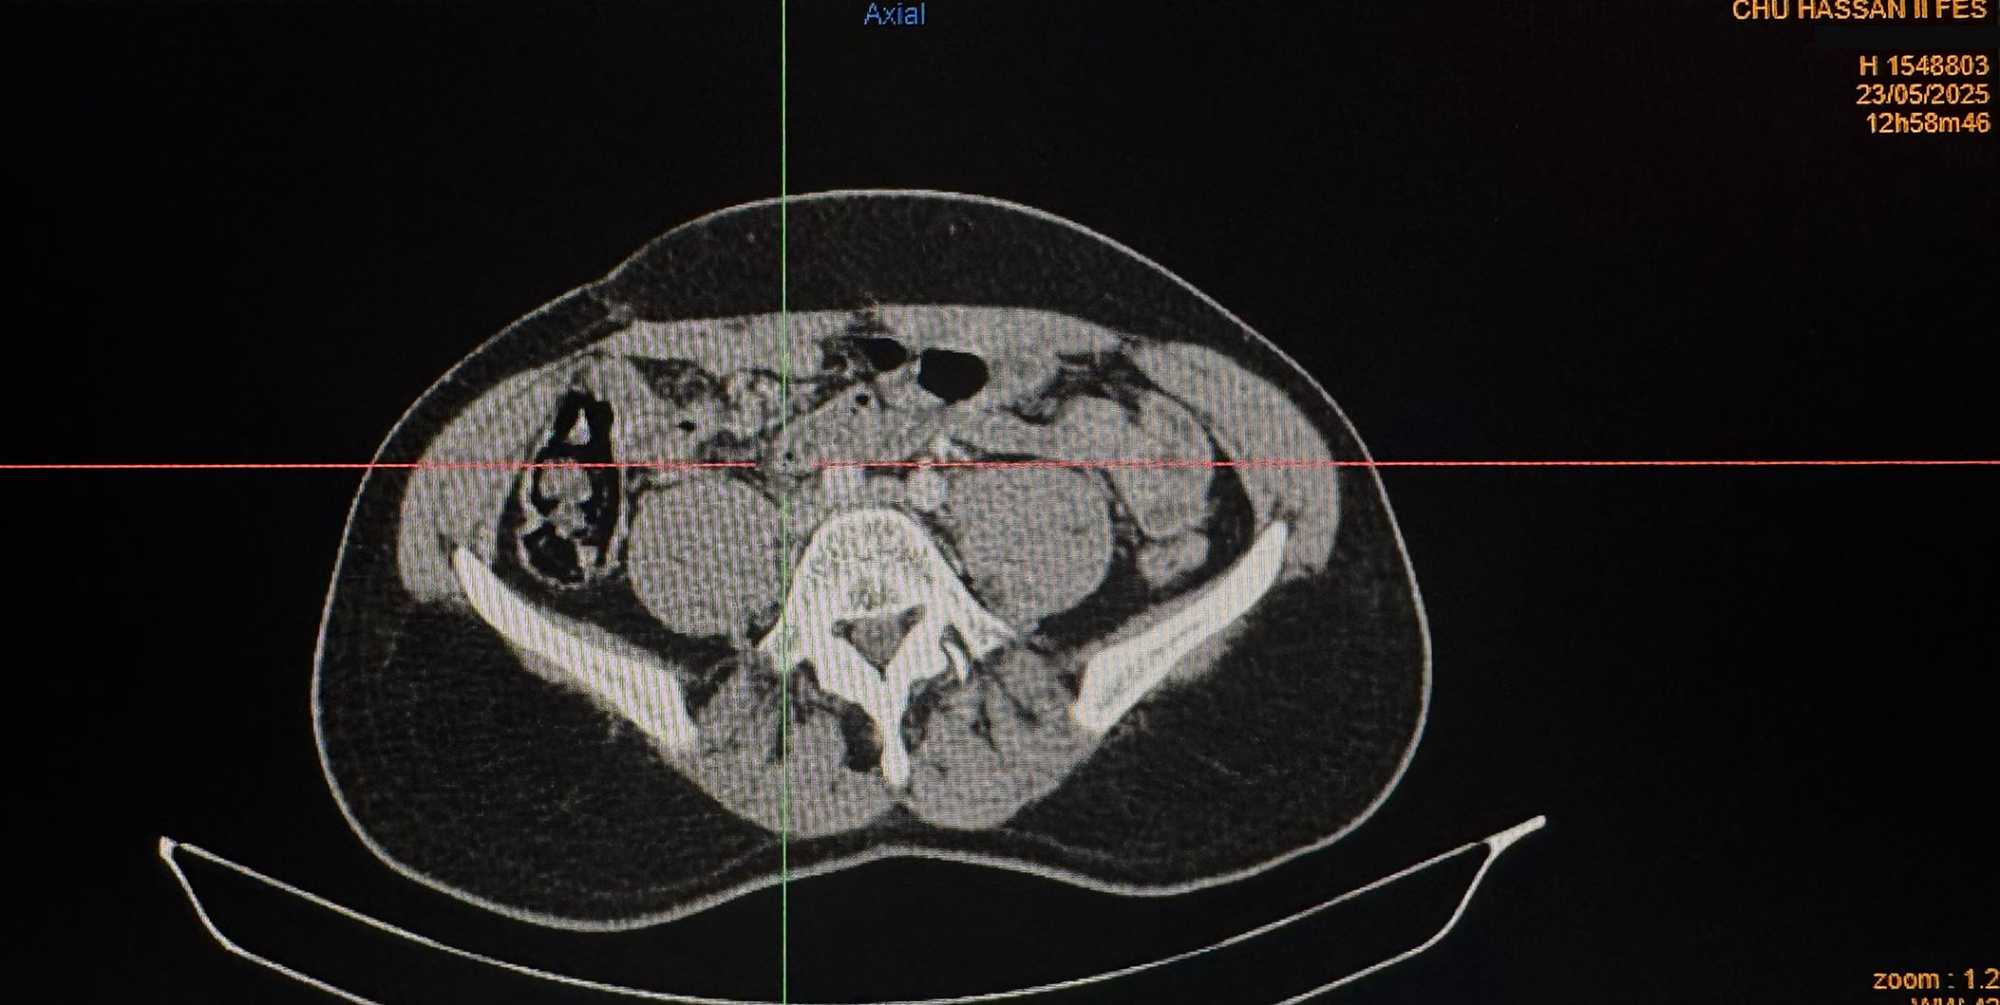

The latest CT scan, performed on May 23, 2025, (Figure 5, Figure 6) showed persistent complete response with no evidence of mass effect or newly emerged suspicious lesions at the thoracic, abdominal, or pelvic levels.

Figure 5. Follow-up axial CT scan showing no evidence of disease-persistent complete response.